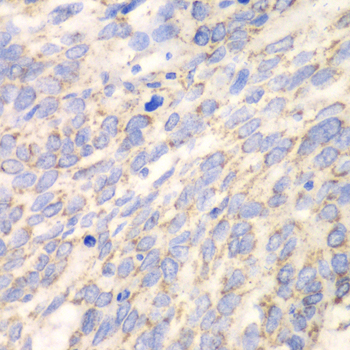

Immunohistochemistry of paraffin-embedded human liver damage using DLD at dilution of 1:100 (40x lens).

Immunohistochemistry of paraffin-embedded human esophageal cancer using DLD at dilution of 1:100 (40x lens).